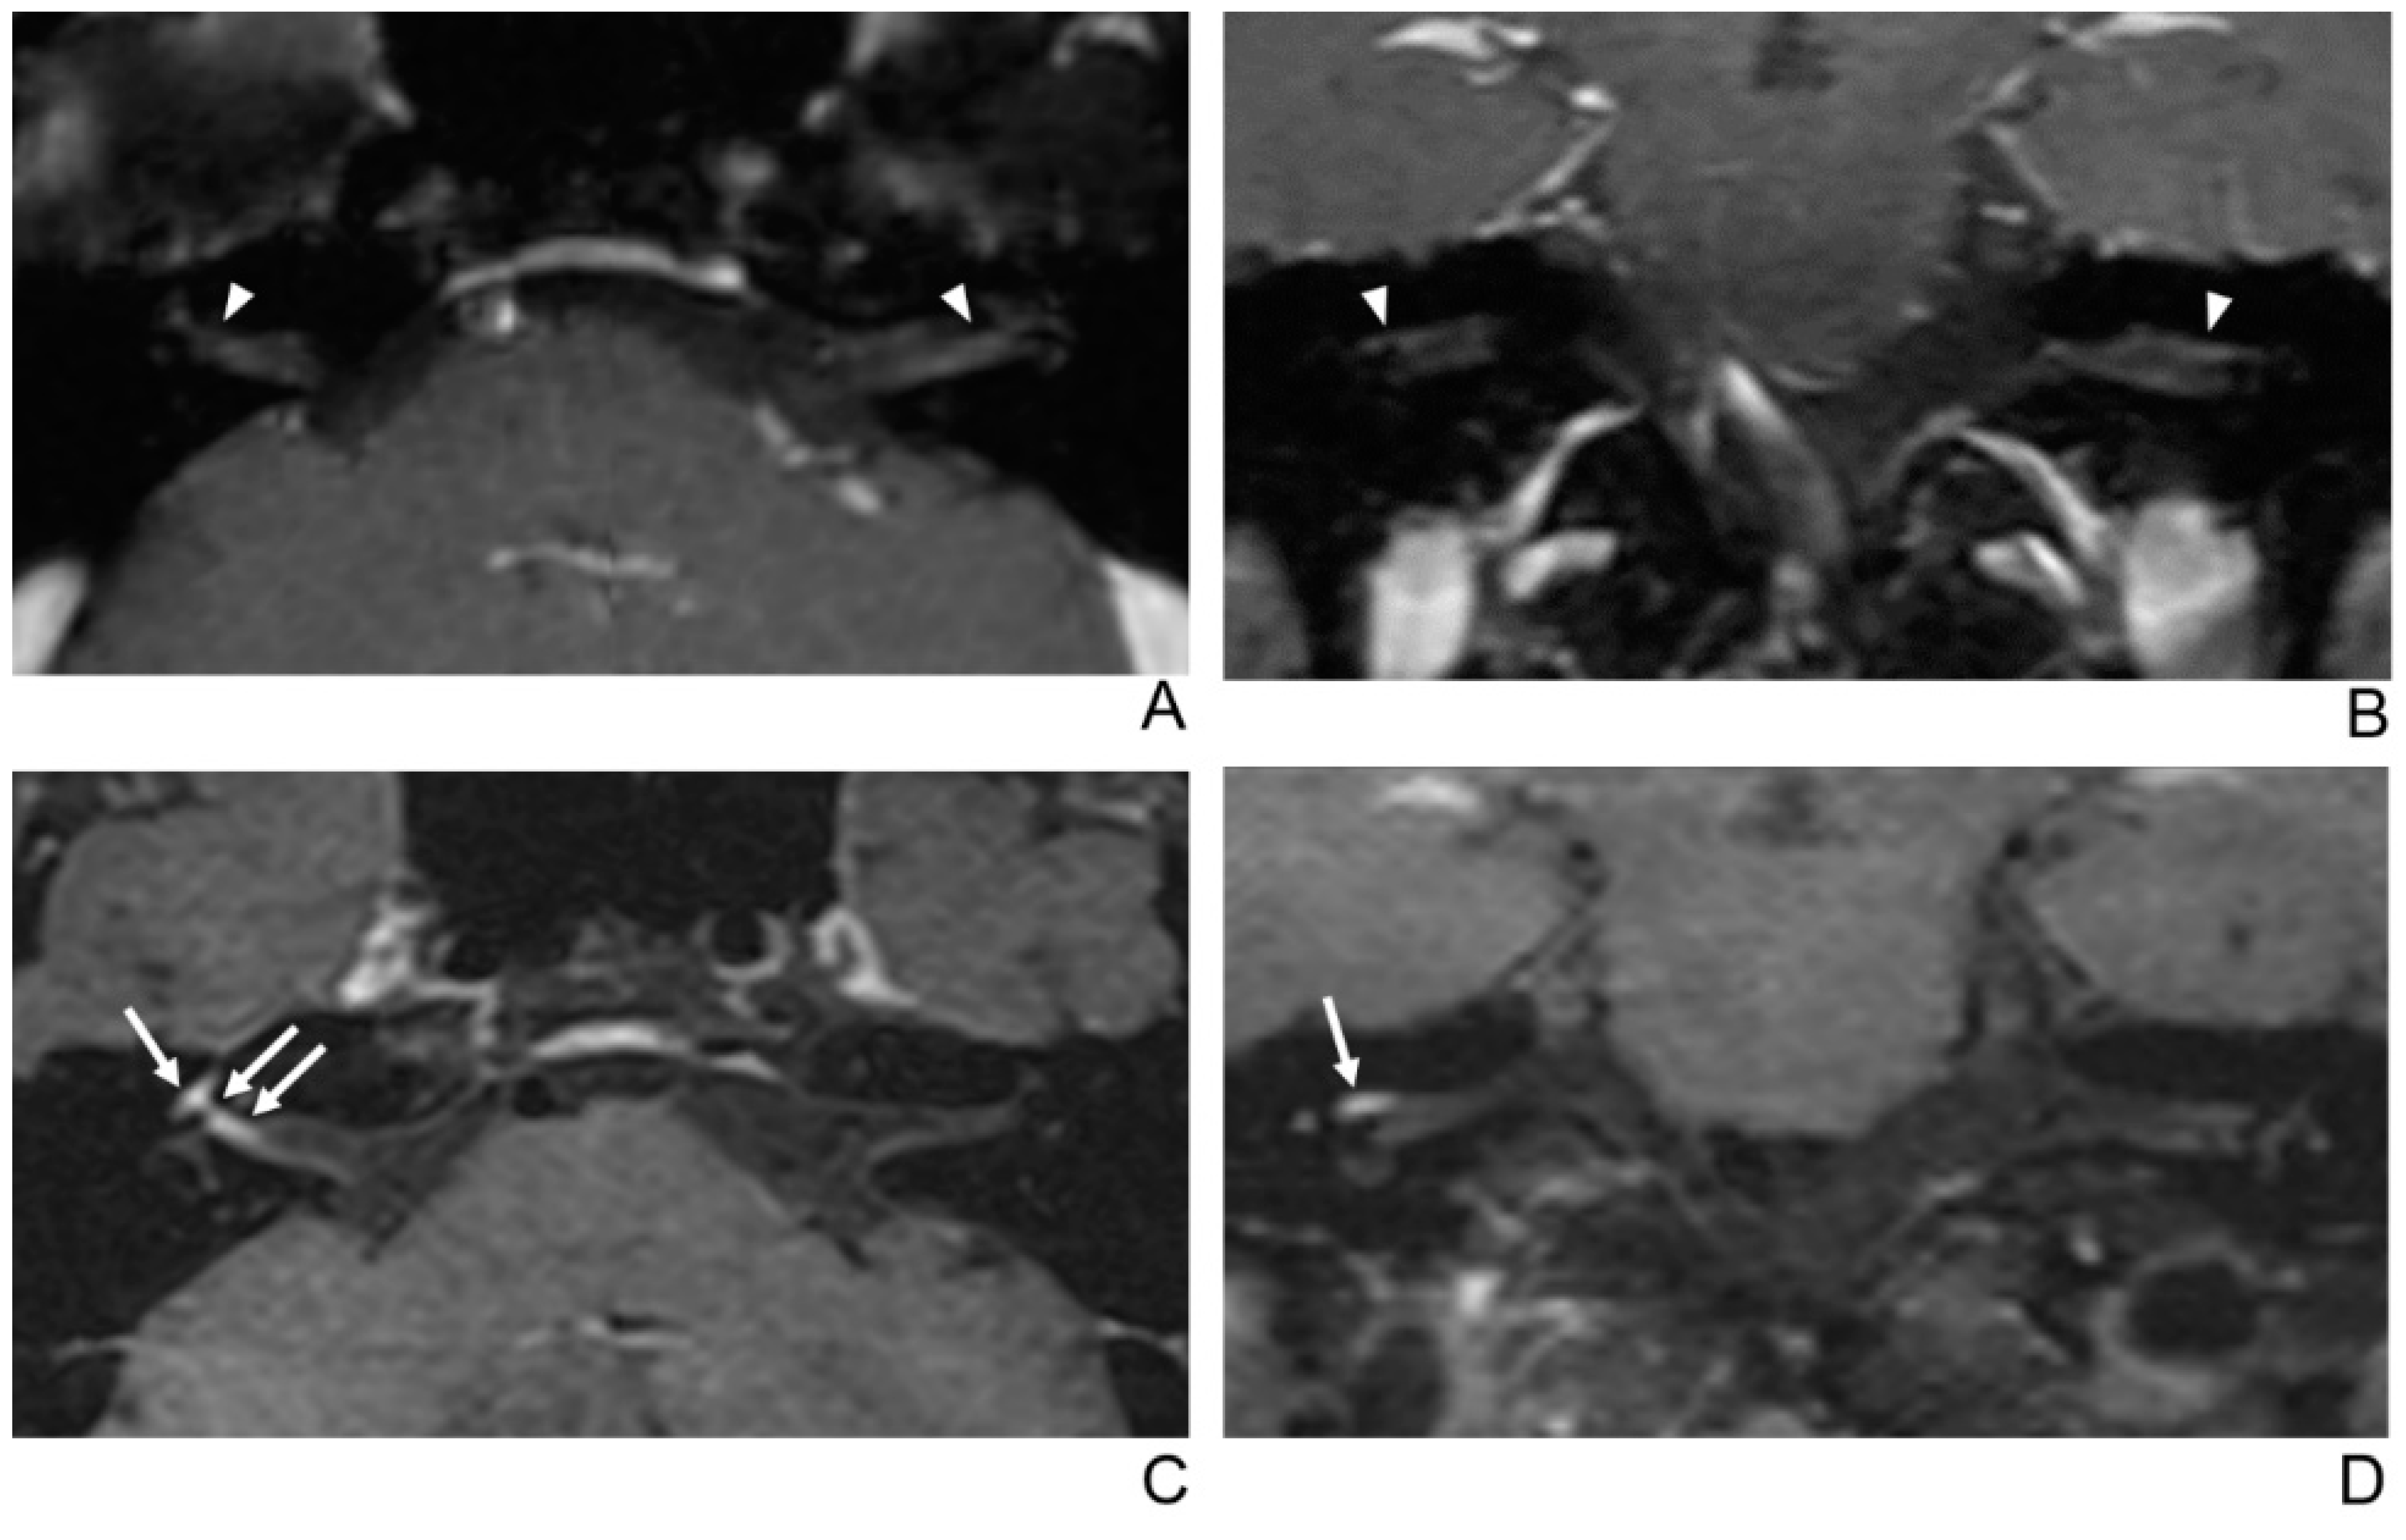

Figure 2.

A 39-year-old male patient with left facial neuritis. (A–D) Paired axial and coronal CE-GRE (A,B) and T1 BB-FSE (C,D) images of the same patient. The left distal canalicular segment of the facial nerve showed asymmetric, intense enhancement in the axial (A) and coronal (B) CE-GRE images (arrowheads). In contrast, the labyrinthine segment showed no definite enhancement, and the anterior genu segment showed moderate degree enhancement and was interpreted by reviewers 1 and 2 as left facial neuritis (2, diagnostic confidence; 3, 0, and 2, visual grades for contrast enhancement (CE) in the canalicular, labyrinthine, and anterior genu segments, respectively). The left facial nerve shows asymmetric intense enhancement in the canalicular, labyrinthine, and anterior genu segments in the axial (C) and coronal (D) T1 BB-FSE images (arrows); it was evaluated by reviewers 1 and 2 as left facial neuritis (2, diagnostic confidence; 3, 2, and 3, visual grades for CE in the canalicular, labyrinthine, and anterior genu segments, respectively). Compared to the CE-GRE images shown earlier, in the T1 BB-FSE image, it can be seen that the contrast-enhanced area in each segment of the facial nerve is longer and wider.